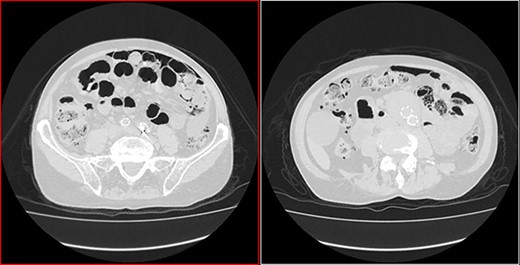

He arrived at the emergency department walking and with no clinical distress. He was complaining of hematuria for a month and worsening of chronic constipation in the last 2 days. Physical examination demonstrated discrete abdominal distention. Laboratory tests showed normal c-reactive protein (CRP), white blood cell count and lactate level. A new CT revealed no change in the previous findings: intestinal pneumatosis and pneumoperitoneum (Figs 2 and 3).

Transversal CT image in lung window showing pneumoperitoneum and pneumatosis intestinalis.

Coronal CT image in lung window showing pneumoperitoneum and ‘bubbles’ within the walls of small intestine and in the mesentery.